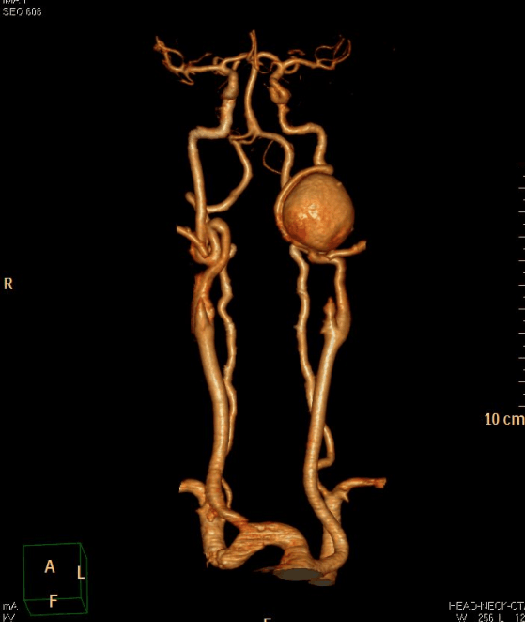

行头颅CTA检查提示:左侧颈内动脉C1段示一巨大动脉瘤,大小约为28.3mm×32.8mm。进一步行全脑血管造影示:左侧颈内动脉颈段巨大动脉瘤,囊状、窄颈,大小约23mm*25mm,瘤体朝前生长;行左侧颈内动脉颈段动脉瘤球囊闭塞试验,术中体感诱发电监测,造影证实左侧颈内动脉起始部完全闭塞约30分钟;闭塞过程中不同时段监测波形、与患者交流等观察病情变化,证实前交通、后交通均开放代偿左侧半球。

术后复查CTA